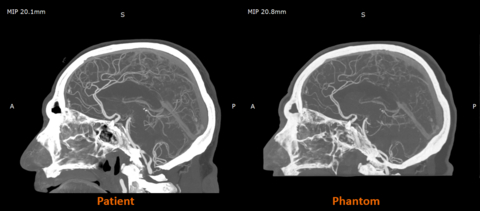

UK-based work with partners such as CPI and Beaumont Hospital is already demonstrating the impact of radiopaque 3D-printed models in practice, with radio-realistic cerebral angiography phantoms being used to improve the fidelity of imaging-based training and create more controlled, repeatable environments for research.

Early research from the Stratasys–Siemens Healthineers collaboration shows that 3D printed RadioMatrix™ phantoms can closely replicate real human tissue in CT imaging, with deviations reported as low as single Hounsfield units (HU) in critical areas such as grey matter and veins. By combining Stratasys’ Digital Anatomy™ 3D printing technology and radiopaque materials with advanced imaging algorithms, the partners are demonstrating anatomically realistic, radio-accurate phantoms that preserve fine anatomical details and pathological variations while offering a more consistent, ethical alternative to cadavers. These models are expected to improve how radiologists validate and optimize CT protocols and accelerate the development of new imaging algorithms for more precise diagnosis and treatment planning.